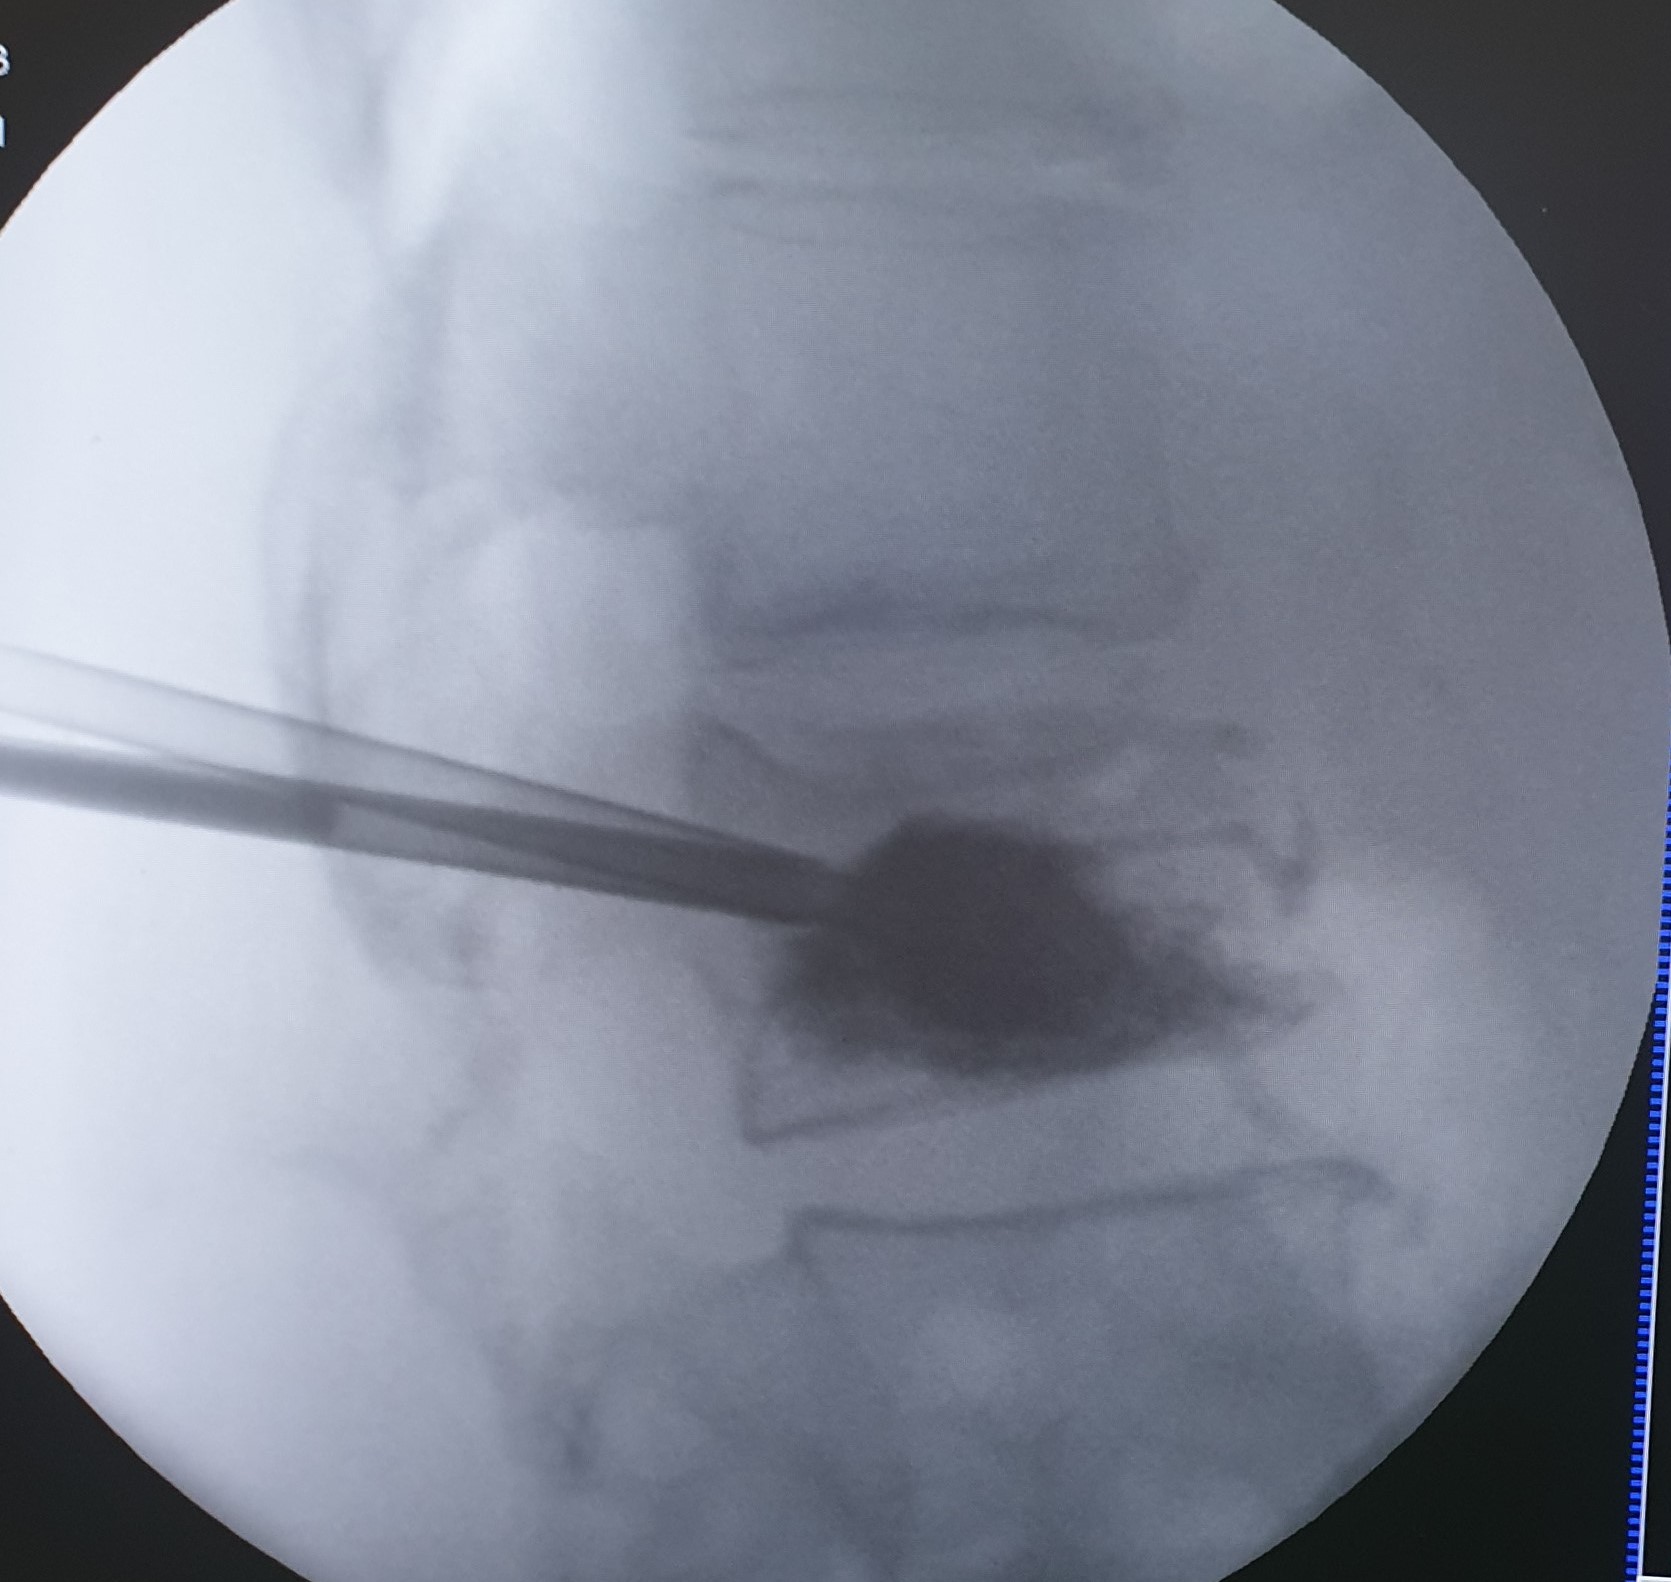

Πρόκειται για συμπιεστικά κατάγματα των σπονδύλων που προκαλούν έντονο πόνο, περιορισμένη κίνηση και ενίοτε κυφωτική παραμόρφωση του σπονδυλικού άξονα. Η κατάρρευση του σπονδυλικού σώματος μπορεί να προκαλέσει πίεση στις νευρικές δομές του σπονδυλικού καναλίου με ανάπτυξη αντίστοιχης νευρολογικής σημειολογίας. Τα οστεοπορωτικά κατάγματα παρατηρούνται συχνότερα στην θωρακική και στην οσφυική μοίρα της σπονδυλικής στήλης και μπορεί να είναι μονήρη ή πολλαπλά.

Ποια είναι η κατάλληλη θεραπευτική προσέγγιση των οστεοπορωτικών καταγμάτων

Η θεραπευτική αντιμετώπιση πρέπει να στοχεύει στη μείωση του πόνου, στην αποκατάσταση της σταθερότητας της σπονδυλικής στήλης και στην αποτροπή της κυφωτικής παραμόρφωσης του σπονδυλικού άξονα.

- Κυφοπλαστική και σπονδυλοπλαστική